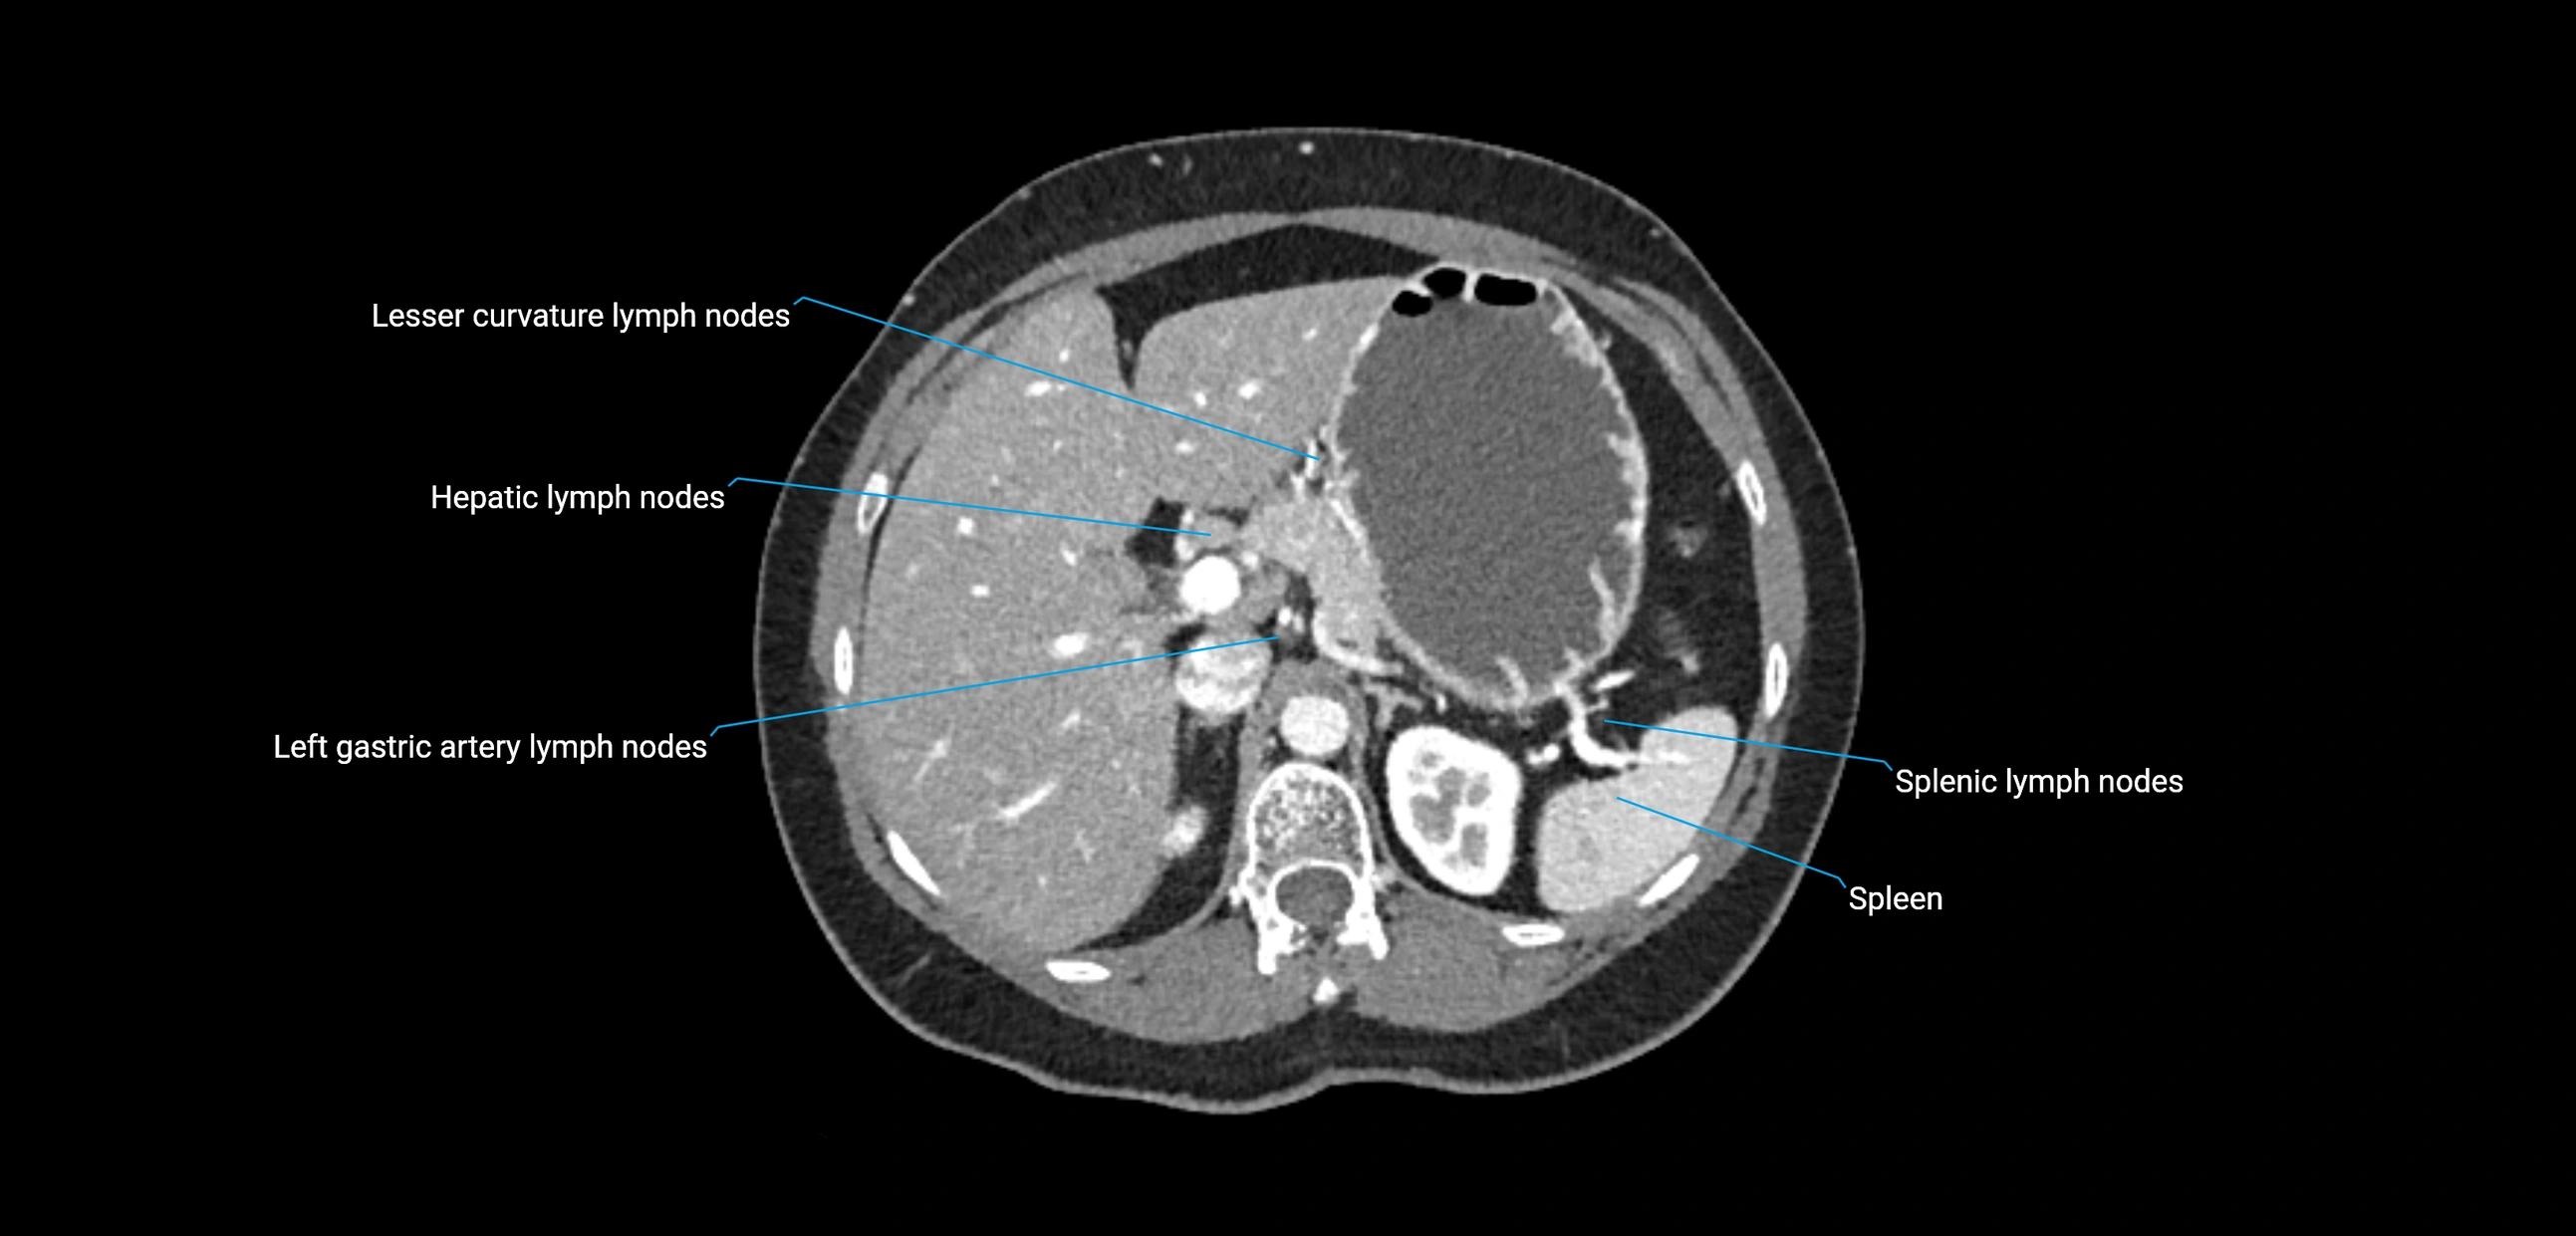

CT image

image